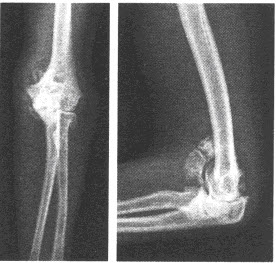

男,21岁,右腘窝部无痛性肿块2年,质硬,较固定,近期局部出现疼痛。结合右股骨正侧位片,最可能的诊断为()

A:骨化性肌炎

B:软骨肉瘤

C:骨化性纤维瘤

D:皮质旁骨肉瘤

E:肿瘤样钙质沉着症